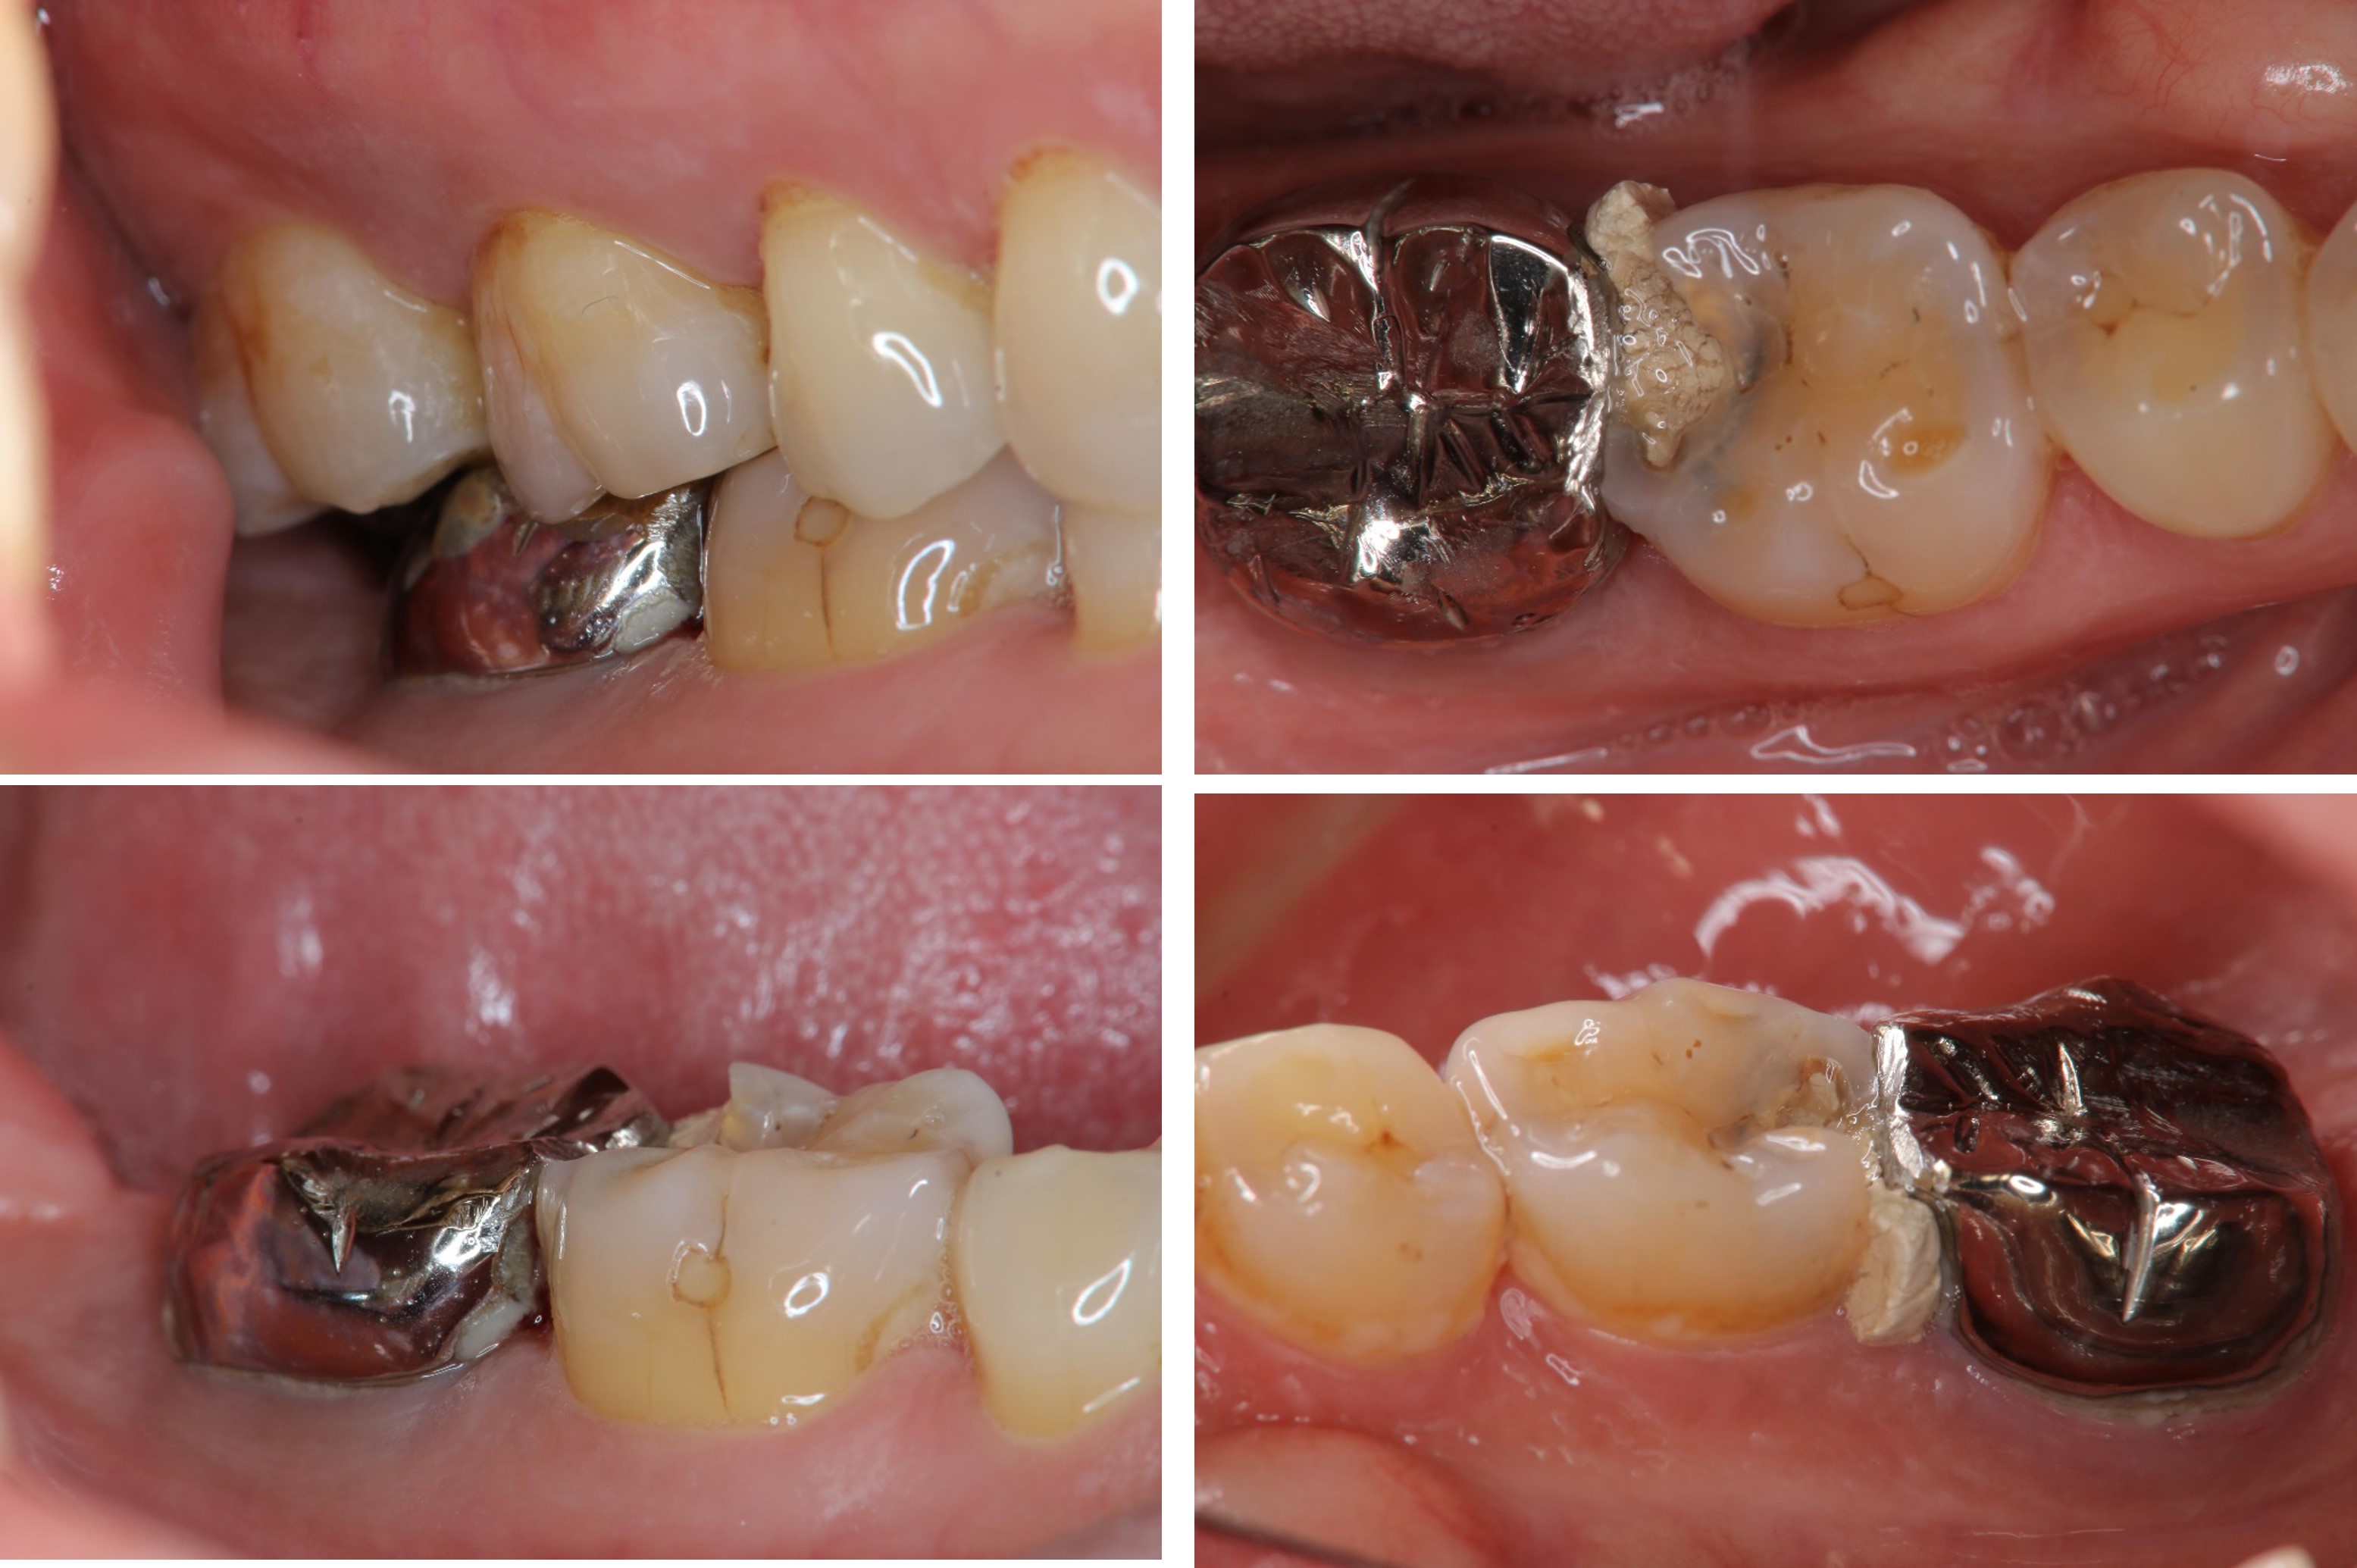

治療前,嚴重蛀牙,咬頭受損

蛀牙未到牙髓